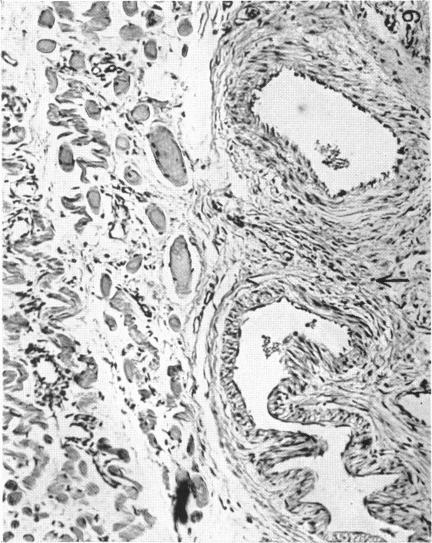

The So-called Interscapular Gland and Tumours Arising Therein.